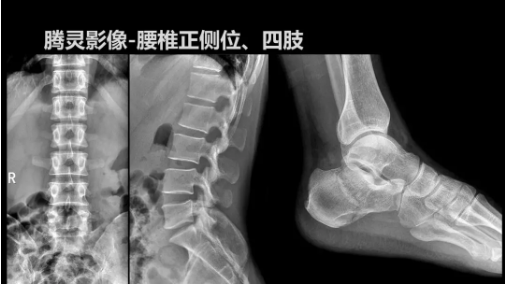

“騰靈”是安健科技的第四代動(dòng)態(tài)DR產(chǎn)品,可實(shí)現(xiàn)全科室應(yīng)用。如各類(lèi)常規(guī)的X線(xiàn)檢查、消化道檢查、骨科檢查、婦科、兒科檢查等。此外,安健科技為“騰靈”在真正意義上實(shí)現(xiàn)多科室、多功能診斷進(jìn)行了多項(xiàng)針對(duì)性設(shè)計(jì)。

相較前代產(chǎn)品,“騰靈”在圖像質(zhì)量方面得到了全面升級(jí),“騰靈”采用17*17非晶硅平板探測(cè)器設(shè)計(jì),采集矩陣達(dá)3072*3072,動(dòng)態(tài)范圍達(dá)16bit,為成像提供超大視野的同時(shí)保證成像質(zhì)量,此外,該款機(jī)型可根據(jù)醫(yī)療機(jī)構(gòu)的差異化需求而選配不同的動(dòng)態(tài)平板探測(cè)器,以此來(lái)適應(yīng)不同階層用戶(hù)所需。